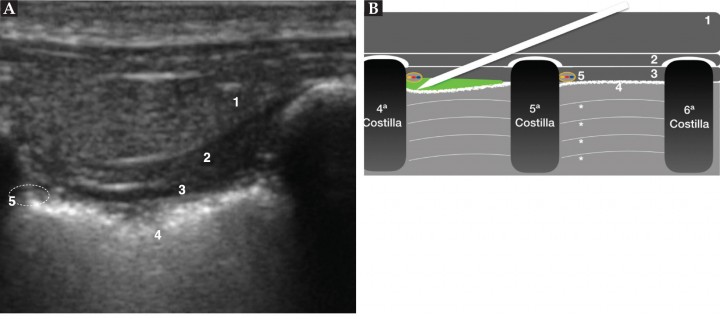

<p>(<strong>A</strong>) Imagen ecográfica del bloqueo intercostal a nivel de T5. Músculo serrato ventral (1), músculo intercostal externo (2), músculo intercostal interno (3), pleura (4), localización del paquete vasculonervioso con el nervio intercostal (5), zona de administración del anestésico (círculo punteado). (<strong>B</strong>) Imagen esquemática del bloqueo intercostal. La aguja se sitúa caudal a la costilla y se muestra el desplazamiento ventral de la pleura al inyectar el anestésico. Músculo serrato ventral (1), músculo intercostal externo (2), músculo intercostal interno (3), pleura (4), paquete vasculonervioso (5; amarillo: nervio intercostal, rojo: arteria intercostal, azul: vena homónima), sombra acústica de las costillas 4ª-5ª-6ª y líneas A del pulmón (*) (ver Vídeo 5).</p>

Figura 8

(A) Imagen ecográfica del bloqueo intercostal a nivel de T5. Músculo serrato ventral (1), músculo intercostal externo (2), músculo intercostal interno (3), pleura (4), localización del paquete vasculonervioso con el nervio intercostal (5), zona de administración del anestésico (círculo punteado). (B) Imagen esquemática del bloqueo intercostal. La aguja se sitúa caudal a la costilla y se muestra el desplazamiento ventral de la pleura al inyectar el anestésico. Músculo serrato ventral (1), músculo intercostal externo (2), músculo intercostal interno (3), pleura (4), paquete vasculonervioso (5; amarillo: nervio intercostal, rojo: arteria intercostal, azul: vena homónima), sombra acústica de las costillas 4ª-5ª-6ª y líneas A del pulmón (*) (ver Vídeo 5).

Para realizar este bloqueo, posicionaremos el transductor lineal (frecuencia 10-15 MHz) perpendicular a las costillas (Fig. 7) para obtener una imagen en la que reconoceremos, de plano más profundo a más superficial, pulmón, pleura, músculo intercostal interno y músculo intercostal externo, estructuras que quedarán separadas por las costillas (Fig. 8). Una vez reconocidas estas estructuras localizaremos la parte caudal de la costilla que sea nuestro objetivo. En este punto, se introducirá una aguja espinal (21G, 50 mm) con un ángulo de 30-45º pasando por todos los planos musculares de la pared torácica hasta situar la punta de la aguja entre el músculo intercostal interno y la pleura, cerca de la parte caudal de la costilla. Entonces, se inyectará un pequeño bolo de suero salino fisiológico y se confirmará la correcta posición de la aguja si se observa que la pleura se desplaza ventralmente15 (Fig. 8B; Vídeo 5). Este bloqueo hay que repetirlo en tantas costillas como sea necesario para producir analgesia en la zona deseada (Fig. 8).